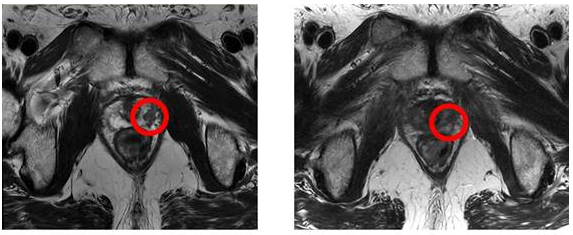

이 환자는 전립선암 2기 진단을 받았으며, 글리슨점수가 3등급이고 전립선특이항원(PSA) 수치가 1mL당 7.9ng로 고위험군에 속하는 상태였습니다. 그러나 4월 말부터 시작한 중입자치료를 한 달간 12회 받은 결과, PSA 수치는 1mL당 0.01ng 미만으로 낮아졌고 자기공명영상(MRI) 상에서 암 조직이 발견되지 않았습니다.

이 중입자치료는 무거운 탄소 입자를 이용하여 암세포를 파괴하는 치료 방법으로, 주변 장기에 피해를 최소화하기 위해 특수 물질 '스페이스 오어(Space OAR)'를 사용합니다. 이로써 치료 중 장기 손상과 합병증 위험을 최소화하면서 치료 안전성을 높일 수 있다고 합니다.